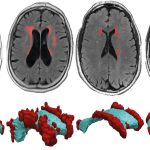

“La malattia da coronavirus SARS-CoV-2 è una malattia infettiva che può presentarsi come una risposta immunitaria incontrollata e iperattiva, causando gravi danni immunologici. I modelli di roditori esistenti non ricapitolano l’immunopatologia sostenuta dei pazienti con malattia grave. Qui descriviamo un modello murino umanizzato di COVID-19 che utilizza il virus adeno-associato per fornire ACE2 umano ai polmoni dei topi MISTRG6 umanizzati. Questo modello ricapitola le risposte immunitarie umane innate e adattative all’infezione da coronavirus 2 acuta e grave fino a 28 giorni dopo l’infezione, con le caratteristiche chiave del COVID-19 cronico, tra cui perdita di peso, RNA virale persistente, patologia polmonare con fibrosi, risposta macrofago infiammatorio umano, una persistente firma genica stimolata dall’interferone e linfopenia delle cellule T. Abbiamo usato questo modello per studiare due terapie per l’immunopatologia: anticorpi derivati ​​dal paziente e steroidi e abbiamo scoperto che gli stessi macrofagi infiammatori, cruciali per contenere l’infezione precoce, in seguito hanno guidato l’immunopatologia. Questo modello consentirà la valutazione dei meccanismi e dei trattamenti della malattia COVID-19″, dicono gli autori.

Hanno scoperto che i topi infetti mostravano gli stessi sintomi dei pazienti umani gravemente malati, come danni ai polmoni, perdita di peso e una risposta immunitaria infiammatoria prolungata e persistente che danneggia i tessuti. Hanno quindi trattato i topi con anticorpi monoclonali forniti da Michel Nussenzweig, un immunologo della Rockefeller University e, come Flavell, un ricercatore dell’HHMI. Questi anticorpi, che mirano specificamente al virus, erano efficaci se somministrati prima o molto presto dopo l’infezione, ma hanno fatto poco per soffocare i sintomi se somministrati nelle fasi successive dell’infezione.